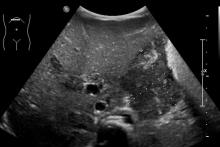

Rozpoznanie: W badaniu USG uwidoczniono w jamie brzusznej rozległe masy guzowate (pomiary między kursorami). Skierowany do dalszej diagnostyki.